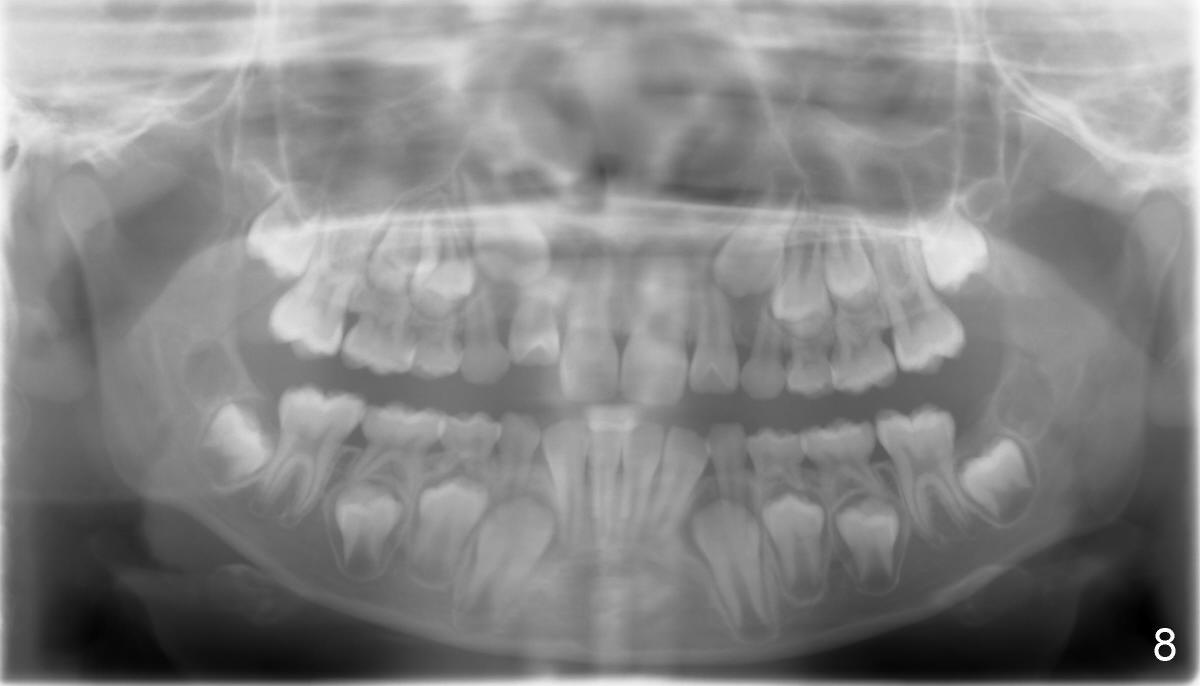

Panramic X-ray was taken when Edward was 6 years 5 months old (Fig.1). His parents and he himself found that the upper right lateral did not erupt at the age of 9 years 2 months (Fig.2-4: *). Gingivectomy was performed using soft tissue laser to expose the incisal edge of the lateral. Five months later, the lateral has erupted partially (Fig.5-8), but the family is concerned about the cosmetic issue. It appears that the upper midline has shifted to the right (Fig.6). Periapical film is planned to take to confirm the relationship between the canine and the lateral.